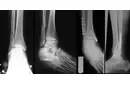

Tedavi Yöntemleri Ayak parmak kemik çıkıntısının tedavisi, durumun şiddetine ve hastanın yaşam kalitesine bağlı olarak değişiklik göstermektedir. Tedavi yöntemleri şunlar olabilir:

Tedavi Seçenekleri konusunda bilgi sahibi olmanız, durumu yönetme konusunda atacağınız adımları kolaylaştıracaktır. Cerrahi müdahale gerekip gerekmediği konusunda uzman görüşü almak elbette önemli. Bu süreçte, doktorunuzun önerdiği tedavi yöntemleri ve bunların olası etkileri hakkında detaylı bilgi almak, karar vermeniz için faydalı olacaktır.